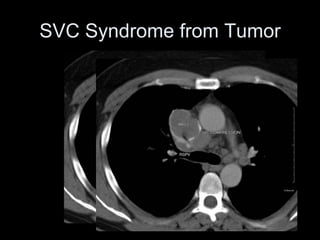

SVC Syndrome from Tumor

LUNG CA

with SVC syndrome